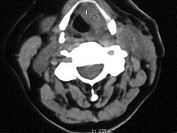

- 单项选择题女,54岁, 喉部异物感约3个月,PE: 左侧声带固定,可见肿物, CT如图,最可能的诊断是 ( )